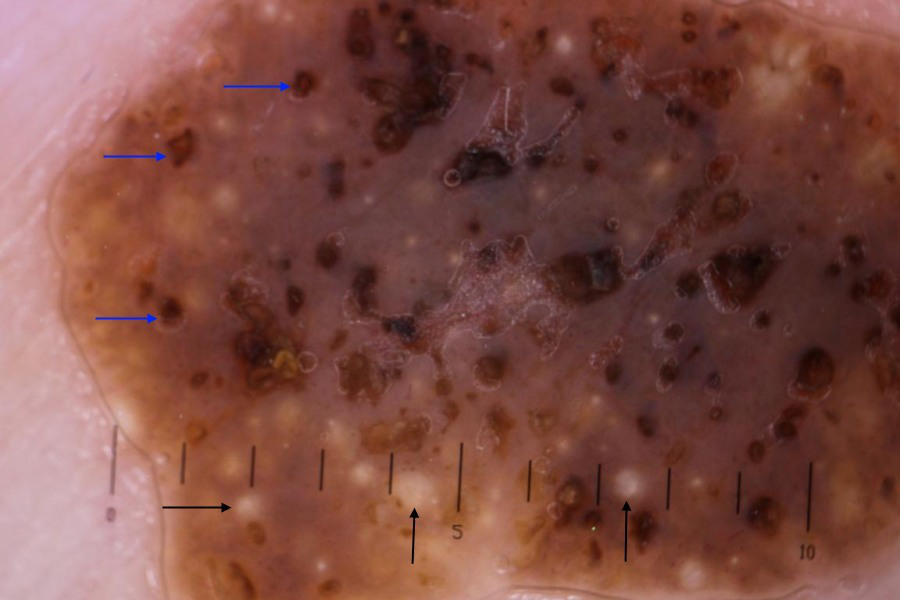

Aparência dermatoscópica típica de ceratose seborreica com cistos similares à milia (setas pretas) e aberturas semelhantes a comedões (setas azuis)

Primary Care Dermatology Society (PCDS); usado com permissão